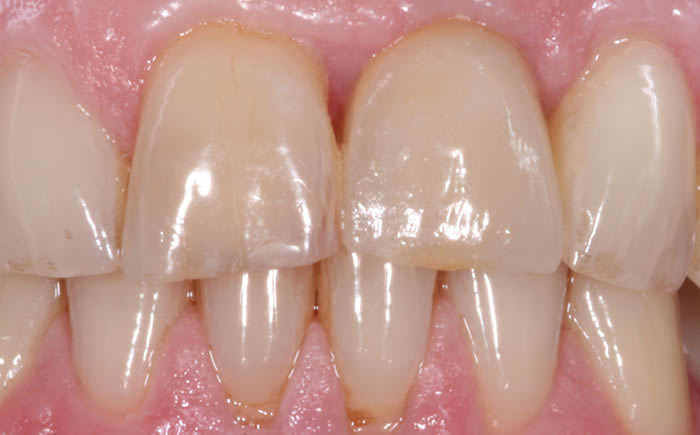

More front teeth replaced by dental implants

Case Three (4 images)